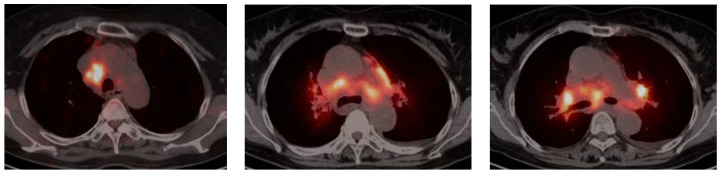

Sarcoidosis is a multisystem granulomatous disease of an unknown aetiology. It can exist in many organs. Pulmonary and intrathoracic lymph nodes are most commonly involved. Lung sarcoidosis is uncommon in Asia. However, due to the large population of our country and the development of bronchoscopy, percutaneous lung puncture, and other medical technologies, the number of pulmonary sarcoidosis patients is on the rise. Pulmonary sarcoidosis patients have no obvious symptoms in the early stage, and the clinical manifestations in the later stage may vary from person to person. Eventually, the disease progresses to life-threatening pulmonary fibrosis. Therefore, patients with pulmonary sarcoidosis should receive a timely diagnosis. In recent years, the imaging features and serologic biomarkers of pulmonary sarcoidosis have been continuously studied. The diagnostic value of imaging and serologic biomarkers for pulmonary sarcoidosis is summarized below.